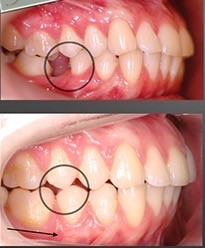

На картинке показан как произошел наклон зубов, расположенных позади промежутка после удаленного нижнего шестого зуба. При этом верхний шестой зуб, “в поисках антагониста”, оказывал избыточную нагрузку на нижние зубы, опускаясь вниз, формировал деформацию верхнего зубного ряда, тем самым усугубляя проблему.

В данных условиях проведение рационального протезирования не представлялось возможным и требовало ортодонтической подготовки. Однако, помимо традиционных вариантов решения подобной проблемы, здесь возможен и альтернативный метод восстановления целостности зубного ряда – ортодонтическое перемещение зубов в зону промежутка после удаления. Именно такая тактика была выбрана в данной клинической ситуации.При таком варианте необходимо обычно переместить седьмой и восьмой зуб на место удаленного шестого при помощи несъёмной брекет- системы .